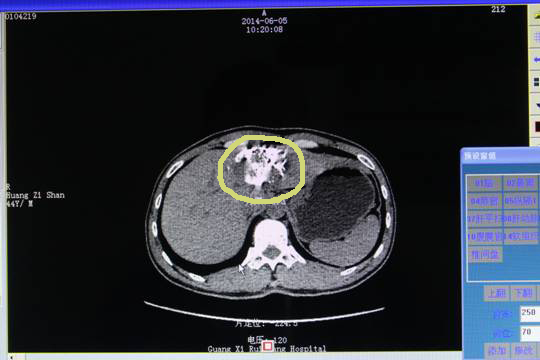

2014年4月18日,按计划行第二次肝动脉栓塞,过程顺利,患者肝功轻度异常,一周后复查恢复正常,出院。复查的CT片中看出黄先生的肿瘤进一步缩小。

第二次栓塞

治疗前需在肿瘤内部或附近放入金标,作为射波刀射线跟踪的目标,以此矫正器官的活动。以下是植入金标后的CT片。

射波刀前植入金标